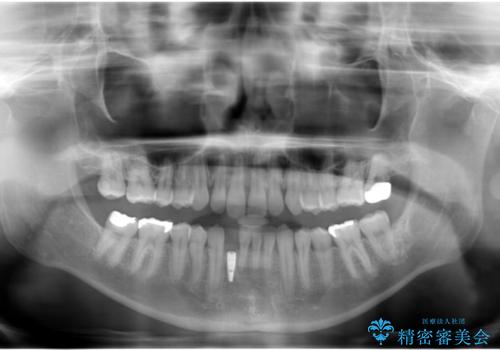

- 下の前歯が1本生まれつき少なかったため、インプラント治療を行いました。

インプラントの前に矯正治療を行い、入れる隙間を確保しました。

ブリッジにすることも可能でしたが、両側の歯が天然歯であること、また、事前に矯正で噛み合わせを整え、幅も確保していたこと、CTにより骨の厚みがある程度あったことを踏まえ、インプラントも可能であるとお話しし、選んでいただきました。

唇側の骨増成もしっかり行い、前歯部インプラントによくある、歯茎が下がって見えることもない、審美的なインプラント補綴ができました。